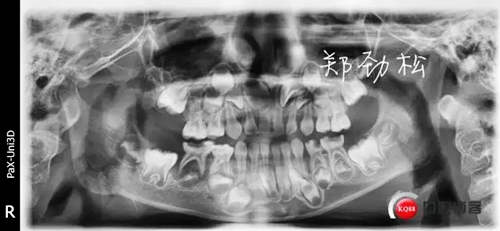

主訴:牙齒反復發(fā)炎近一年

現病史:患兒父親代述一年前患兒前牙在外院做過根管治療,后前牙唇側牙齦反復膿腫前來就診。

檢查:7A牙體變色,舌側有充填物,叩診(++),松一度,冷熱刺激無反應,唇側牙齦紅腫有一瘺管。

診斷:7A慢性根尖炎

處置:開隨,去除根充物后沖洗引流。

此病例術后取出根充物發(fā)現其中有兩根牙膠尖,其實大家都知道乳牙的牙根隨著恒牙的萌出會逐漸吸收,而牙膠尖不能被吸收,所以牙膠尖不能夠用作乳牙根充,我常規(guī)選擇vitapex糊劑作為乳牙的根充材料。